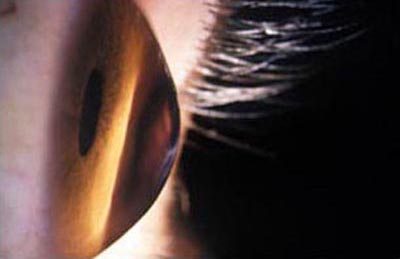

Queratocono

Queratocono

Queratografía

Es una enfermedad ectásica no inflamatoria que afecta la curvatura y el espesor de la córnea provocando su protrusión e irregularidad; es relativamente frecuente con una prevalencia del 54.5 por 100.000 (0.05%). Se da en todos los grupos étnicos, es bilateral y no existe predominio sexual. Su ocurrencia es mayor en personas que habitan tierras altas.

Su etiología todavía no está resuelta; entre 6 y 15% de los pacientes con queratocono, tienen familiares afectados. Se asocia a una larga lista de enfermedades sistémicas, pero su forma de presentación es esporádica y aislada. Su asociación mas frecuente es con la compresión, frote y restregado ocular, como trauma mecánico crónico.

Aparece en la pubertad, y por lo general el ritmo de progresión es mayor cuanto más joven es el paciente afectado. A medida que el queratocono progresa, la agudeza visual se ve comprometida por la distorsión que el cono genera, llegando a inhabilitar a la persona afectada para el desarrollo de una vida normal.